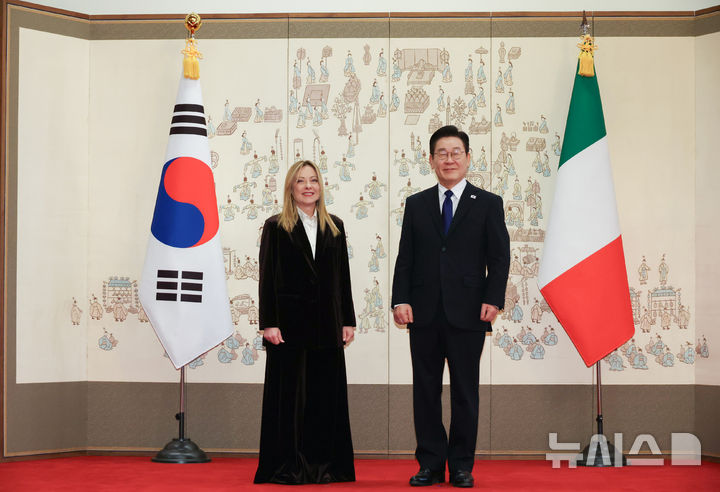

![[부산=뉴시스] 인제대학교 해운대백병원 전경. (사진=해운대백병원 제공) *재판매 및 DB 금지](https://img1.newsis.com/2023/09/04/NISI20230904_0001356396_web.jpg?rnd=20230904184741)

[부산=뉴시스] 인제대학교 해운대백병원 전경. (사진=해운대백병원 제공) *재판매 및 DB 금지

[부산=뉴시스]권태완 기자 = 인제대학교 해운대백병원은 신경중재팀이 뇌동맥류 '코일색전술' 3000례를 돌파했다고 4일 밝혔다.

신경중재팀은 2017년 말 1500례 달성 이후 불과 6년이 지나지 않아 3000례를 달성했으며, 매년 300건에 육박하는 시술을 성공적으로 마쳤다.

최근에는 코일색전술 외에도 '스텐트를 활용한 혈류전환술', 'WEB 기구를 통한 색전술' 등 최신화된 치료 방법도 개발됐으며, 해운대백병원 신경중재팀은 이러한 술기를 모두 포함해 지난달 말 3000례를 달성했다.

해운대백병원 관계자는 환자들에게 발생한 합병증은 1% 미만에 불과하다고 설명했다.

신경외과 진성철 교수는 "앞으로도 환자들에게 최상의 치료를 제공하고, 지속적인 연구와 교육을 통해 기술력을 향상해 나아갈 것"이라며, "부산, 울산, 경남권역을 넘어 국내 최고 뇌혈관 치료센터로의 도약할 것"이라고 말했다.